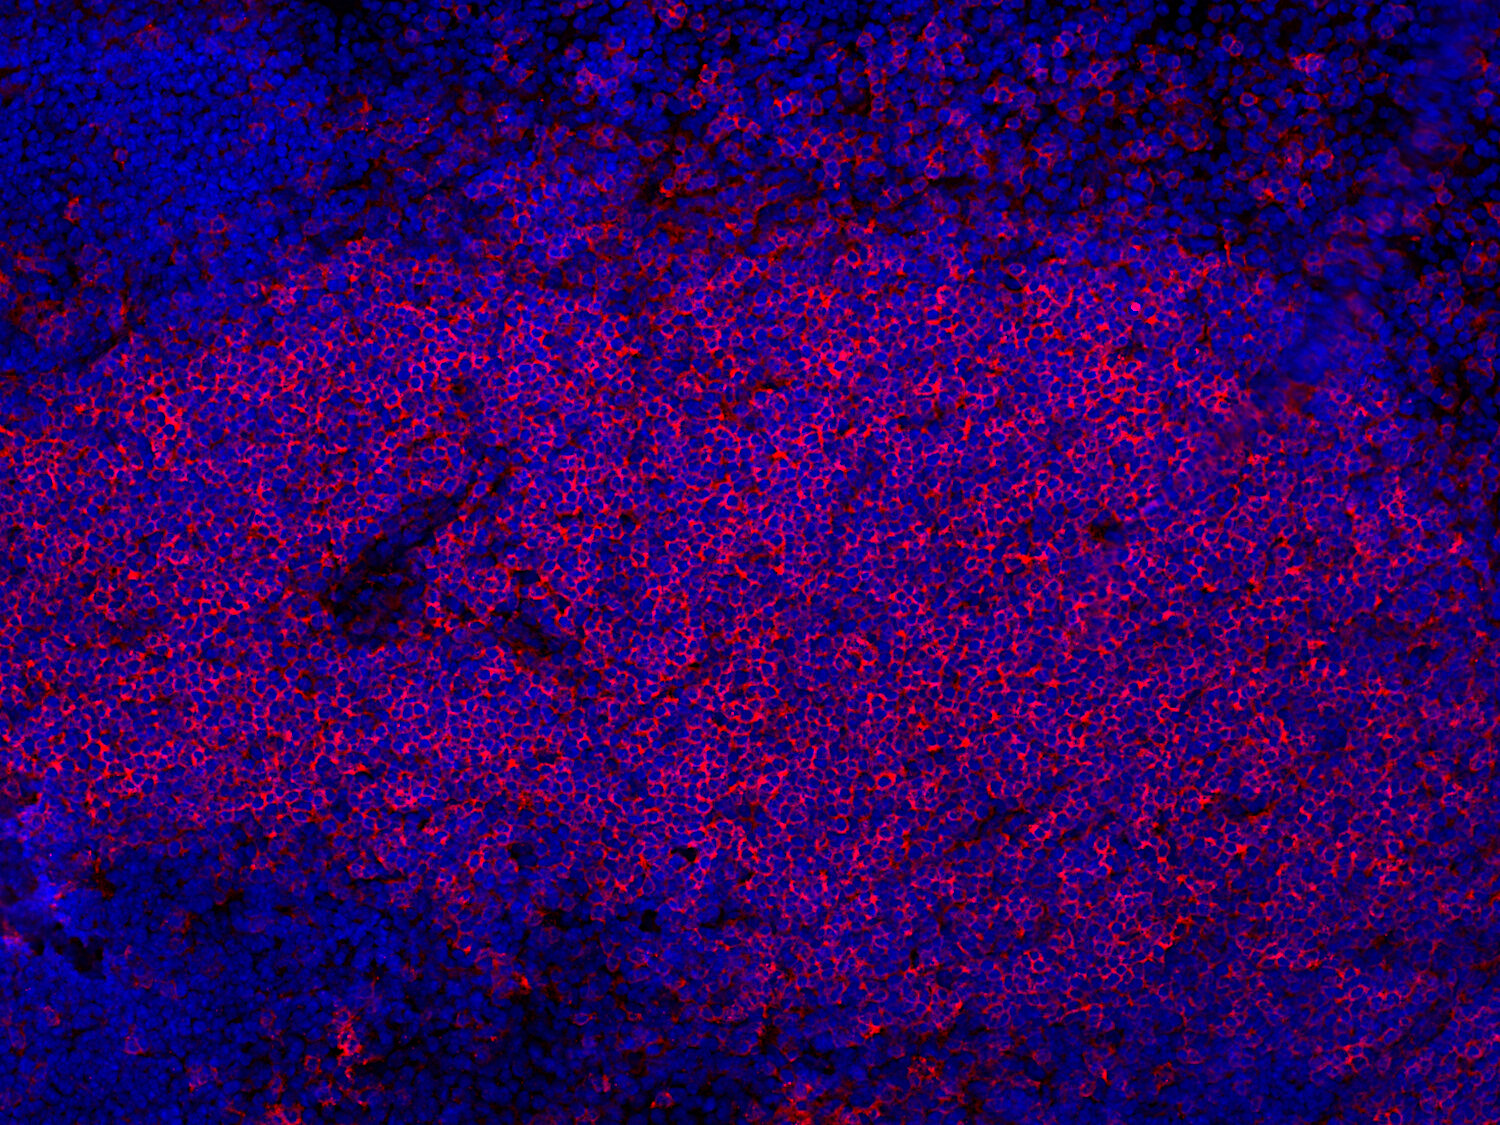

IHC: 1 : 100 (see remarks) gallery

IHC-Fr: 1 : 100 (see remarks) gallery

Immunohistochemistry (IHC) on 4% PFA perfusion fixed tissue with 24h PFA post fixation. Immunoreactivity is usually revealed by fluorescence or a chromogenic substrate. Some antibodies require special fixation methods or antigen retrieval steps. For details, please refer to the ”Remarks” section.

Immunohistochemistry on fresh frozen (IHC-Fr) cryo-tissue-sections. In contrast to standard PFA perfusion fixed tissues, fresh frozen cryo-tissue-sections can be variably postfixed with alcohols, acetone or PFA. Alcohol or acetone fixation is e.g. of advantage for antigens masked by PFA crosslinking. For recommended postfixation, please refer to the ”Remarks” section. Immunoreactivity is usually revealed by fluorescence or a chromogenic substrate.

IHC: Antigen retrieval with citrate buffer pH 6 is required.

IHC-Fr: The following fixatives are possible: methanol, 4% formaldehyde/PFA.